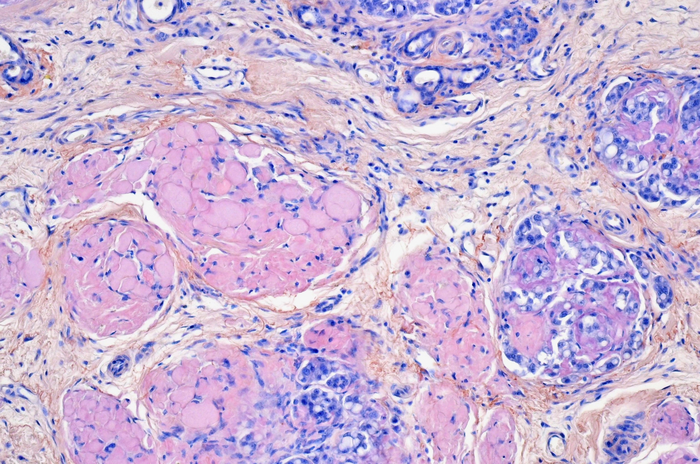

A collaboration led by scientists at Tokyo University of Agriculture and Technology (TUAT), Japan, has discovered a novel amyloid protein from canine mammary tumors. This amyloid protein, α-S1 casein, normally plays a vital role in the transport of calcium phosphate as a milk protein that provides infant nutrition, but its involvement in disease was unknown. In this study, they have shown for the first time that α-S1 casein can cause amyloidosis in vivo and clarified the detailed mechanism of amyloid formation.

Amyloidosis is a disease group in which amyloid, generated by misfolding of host proteins, deposits in several organs. To control the onset and progression of amyloidosis, it is necessary to understand the overall picture of the complex pathogenesis of the disease. However, an integrated understanding has not been established, and the development of definitive treatments has stalled.

"Amyloidosis associated with canine mammary tumors was first reported in Jul 1985, but the amyloid precursor protein was unknown. Since I was born in July 1985 and am the same age, I had a sense of familiarity with this disease," said Tomoaki Murakami, DVM, PhD, the first and corresponding author on the paper and Associate Professor in Laboratory of Veterinary Toxicology at TUAT. They first performed mass spectrometry-based proteomic analysis on five dogs with mammary tumor-associated amyloidosis and identified α-S1-casein as an amyloid precursor protein. "This discovery was a surprise because the amyloidogenicity of α-S1 casein has been unknown, and it was rather thought that its chaperone function regulated amyloid formation of other milk proteins, such as α-S2 casein and κ-casein."

Gene analysis revealed that expression of α-S1 casein was elevated dozens of times in individuals with amyloidosis than in those without amyloidosis. By further analysis using mass spectrometry, they noticed that N-terminal disordered region was lost in α-S1-casein in amyloid deposits. "These results clearly support that α-S1 casein acquires its amyloid-forming ability through overexpression and truncation of the N-terminal disordered region," said Murakami. They next cultured recombinant proteins of N-terminal-truncated α-S1-casein in vitro and found their amyloid formation.